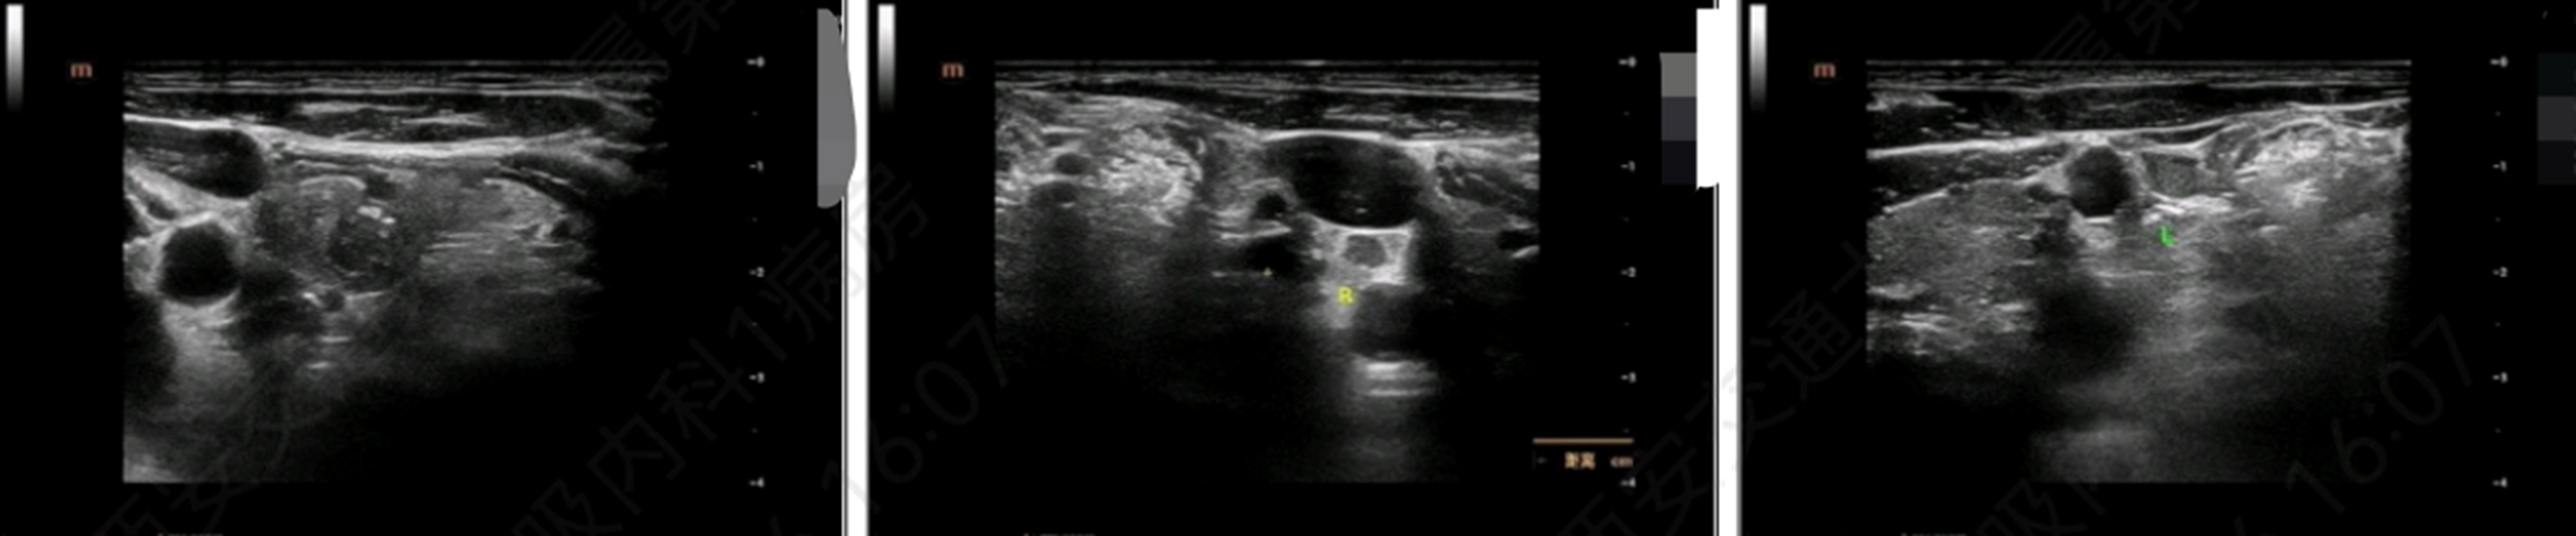

• 甲状腺彩超示,甲状腺右叶下极及左叶中下部结节 TI-RADS 5类,甲状腺右叶中下部结节 TI-RADS 4类,甲状腺双叶小结节 TI-RADS 2-3类,左侧颈部IV淋巴结回声不均匀,且在超声引导下甲状腺右叶下极低回声结节+甲状腺左叶中下部低回声结节+左侧颈部IV区淋巴结及包埋蜡块FNA;

图4 甲状腺彩超